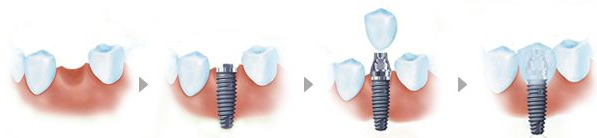

种植牙是一种利用生物材料,通过高科技手段修复缺牙的治疗技术。种值牙就是将人工材料制成的种植体(即“人工牙根”)植入缺牙区的牙槽骨内,上部的基桩暴露在口腔内,再在基桩上接上烤瓷牙。种植牙的手术很小,无需住院,手术完全无痛,术后即可进食。种植术后3-6个月待种植牙牙根与颌骨形成骨性结合后,即可在种植牙根上制作假牙。治疗过程中可以戴用暂时性的假牙。种植手术的最佳时机是拔牙后2月至1年。